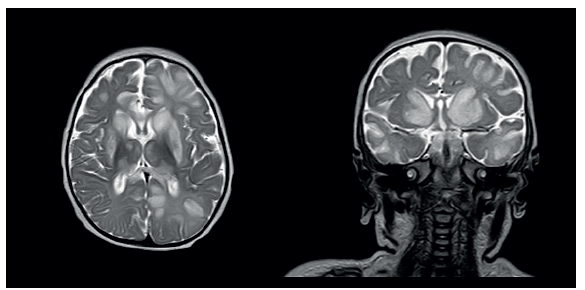

Los paraclínicos del ingreso mostraron acidemia metabólica con aumento del anion GAP, hiperamonemia leve (en 90 umol/L, normal inferior a 75 umol/L) y lactato elevado (5,8 mmol/L, normal inferior a 2 mmol/L). Se sospecha una enfermedad neurometabólica de tipo aciduria orgánica primaria debido a la presencia de acidemia metabólica hiperlactatémica e hiperamonemia leve. Además, en la TC simple de cráneo se observó hipodensidad bilateral en el cuerpo estriado y en la parte anterior del cíngulo derecho, sugestivo de encefalopatía necrotizante subaguda y SL. Se inicia administración de cofactores: riboflavina, tiamina, L carnitina, coenzima Q10, ácido α-lipoico y biotina. Las imágenes de RM cerebral simple con espectroscopia mostraron lesiones de aspecto necrotizante en núcleos basales con compromiso de núcleos caudados, putámenes y tálamos, edema citotóxico cortical, espectroscopía con aumento de la colina (Cho), disminución del N acetil aspartato (NAA) y pico de lactato, hallazgos característicos de la espectroscopia por RM en SL (figuras 1 y 2).

Resonancia magnética secuencia T2: A y B en corte coronal y axial a la altura de los núcleos de la base, donde se evidencian hiperintensidades que comprometen la cabeza de los núcleos caudados, putámenes y talamos. Adicionalmente, se presentan lesiones hiperintensas en la sustancia blanca subcortical de los lóbulos frontales de predominio izquierdo, así como en el lóbulo occipital y temporal izquierdo.

Figura 1: Resonancia magnética secuencia T2: A y B en corte coronal y axial a la altura de los núcleos de la base, donde se evidencian hiperintensidades que comprometen la cabeza de los núcleos caudados, putámenes y talamos. Adicionalmente, se presentan lesiones hiperintensas en la sustancia blanca subcortical de los lóbulos frontales de predominio izquierdo, así como en el lóbulo occipital y temporal izquierdo.

Esta mutación en HIBCH ocasiona episodios de cetoacidosis, niveles elevados de piruvato y lactato en el líquido cefalorraquídeo y regresión de los hitos del desarrollo en el transcurso del primer año de vida. En las imágenes por RM cerebral es típica la alteración de señal en la secuencia T2 de los ganglios basales en forma bilateral y tronco encefálico, diferentes grados de atrofia de la sustancia blanca, y pico de lactato determinado mediante espectroscopia 13. Este hallazgo neurorradiológico ha sido común en los tres casos colombianos reportados a la fecha. Más infrecuentemente, se ha descrito la afectación de la sustancia blanca cerebral, de la sustancia negra, del núcleo rojo, de la médula espinal y del cerebelo 5,7. Nuestra paciente falleció por causa directa de una insuficiencia respiratoria aguda y en la MRI cerebral se ha reportado afectación medular caudal de la médula espinal, hallazgo relacionado con disfunción del centro respiratorio 14.